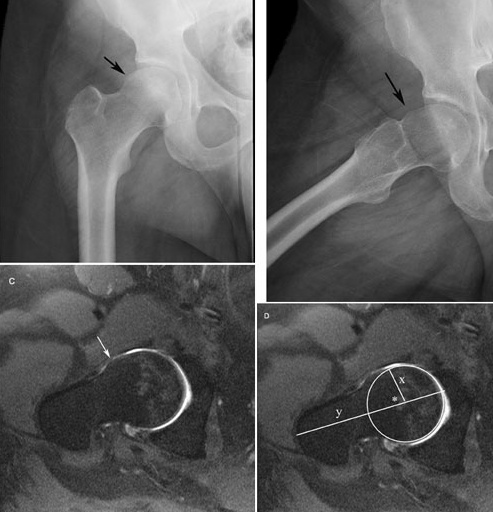

Femoro Acetabular Impingement Syndrome comes in two forms, which usually coexist.

The first, pincer, is a deformity of the acetabulum. The second, cam, is a growth on the neck of the femur.

In CAM there is an abnormality at the level of the anterior femoral head, or the head-neck junction, resulting in increased femoral neck/head - acetabular rim contact. Cartilaginous lesions form along either the postero-inferior or superior aspects of the acetabulum, causing stiffness and limiting the range of motion. A hard end-feel is characteristic.

There is limitation of flexion, often adduction, and characteristically limited INTERNAL ROTATION, with a hard end-feel (in the young person, continuing of course into degenerative old-age arthritis, indistinguishable from conventional Cox arthritis, if not recognised and appropriately treated).

In Pincer-Femero Acetabular Impingement Syndrome - the acetabulum gives increased coverage of the femoral head - femoral neck juntion, limiting the full range of motion of the hip. In particular, EXTERNAL ROTATION of the flexed hip is characteristic, again with a hard end-feel.